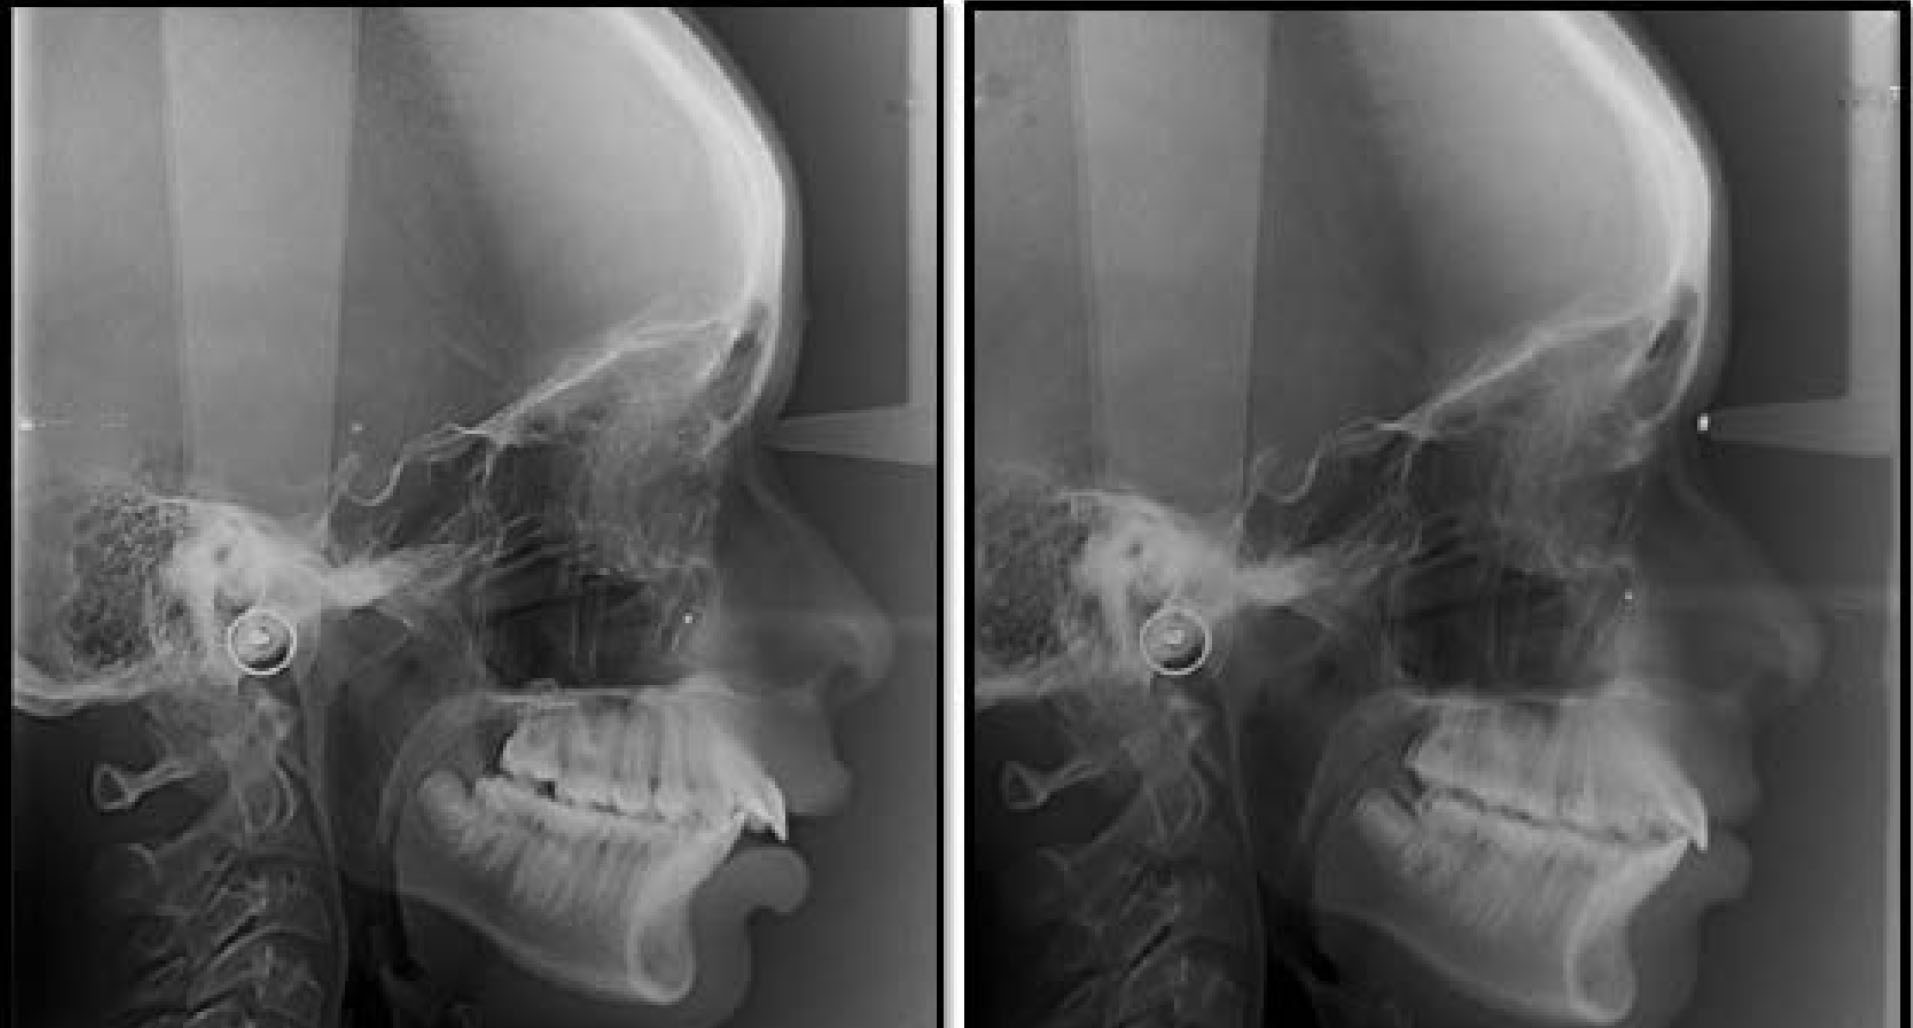

Standardized lateral cephalometric radiographs ().

Standardized lateral cephalometric radiographs at T1 and T2.

Skeletal and dental effects were assessed through Pancherz’s SO analysis ().

Figure 6.

SO analysis

to assess post-functional treatment changes with T1 tracing in black and T2 in red.

The pre-functional treatment changes (T1) were traced in black and the post-functional changes (T2) in red.

Reference planes for the analysis were: NSL (anterior cranial base); OL (occlusal line); MP (mandibular plane), and OLp (occlusal line perpendicular).

The OL and the OLp from T1 lateral cephalogram were used as a reference plane and transferred to T2 by superimposing the tracings on the NSL with S as a registration point.

Skeletal and dental changes were appraised through the SO analysis (sagittal occlusal analysis) developed by Pancherz ().

This analysis was carried out in addition to traditional jaw base parameters like SNA, SNB, and ANB. The SO analysis also facilitates a comparison between the present study on the Flip-Lock Herbst appliance and previous studies on the Herbst appliance.